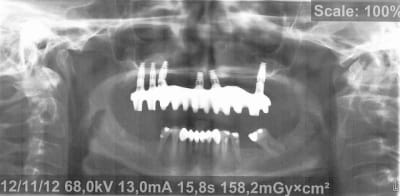

Voici donc les panos pour vos petits yeux ébahis

Profitez bien : elles sont ds l ordre chronologique...

(On est loin de tout comprendre sur les panos un peu floue, si ce n'est qu'à la fin totu est perdu)

Je vous donne une petite info : le comblement au BioOss a échoué largement...et on lui propose des greffes crâniennes à présent

Qu en pensez vous ??????????

- On y voit un manque flagrant de densité du greffon

- On y voit une perte d'un implant sans changement de plan de traitement, on se retrouve avec un seul implant du coté où mastique le patient

- On y voit une armature qui baille sur le seul implant qui reste secteur 2, et donc manque de passivité

- On y voit ce qui devait arriver,

Mais je vois aucun rapport entre l’échec et la nature du matériau mis en place dans le sinus....